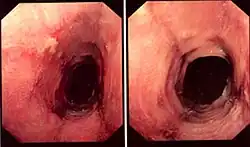

While the diagnosis of lymphocytic esophagitis depends on the biopsy results, certain changes can be visualized directly at the time of endoscopy. The esophagus may be narrow in calibre,[5] may show multiple rings,[5] redness,[5] linear furrows[1] or the mucosal lining may slide demonstrating a "crepe-paper" appearance.[1] Complications such as strictures of the esophagus can also be detected with endoscopy.[5] These changes are very similar to those found in eosinophilic esophagitis, a more common and better understood esophageal disorder thought to be of allergic origin.[5] Narrow-band imaging with magnification endoscopy is another imaging modality that can show characteristic changes of lymphocytic esophagitis.[7]